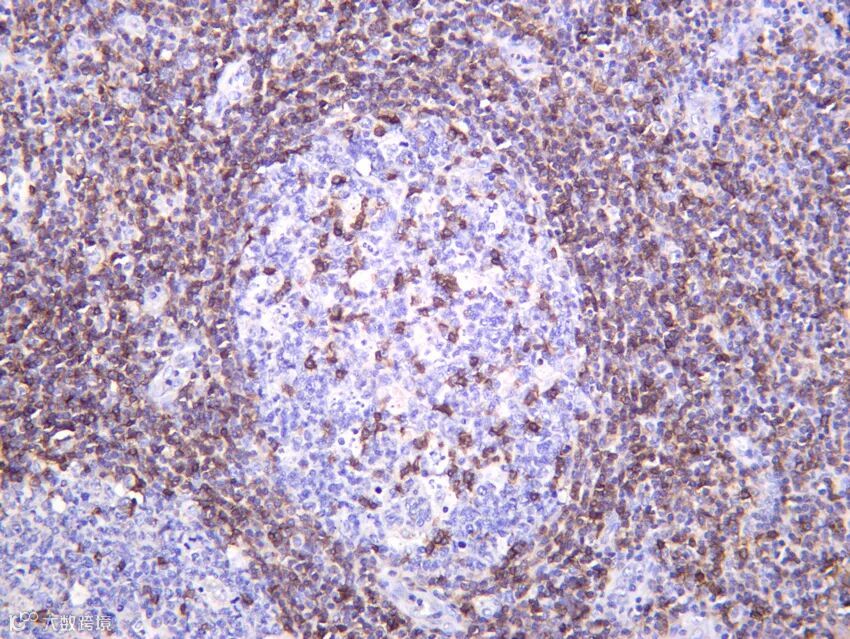

CD69 (PT1700R) PT™ Rabbit mAb

Reactivity:Human

Applications:WB, IHC, IF, IP, ELISA

关键词:早期活化标志物、淋巴细胞激活、组织驻留

CD69 是 C 型凝集素受体,在 T、B、NK 细胞活化后数小时内表达,抑制 S1P1 介导的淋巴细胞外流,促进组织驻留。它是肿瘤浸润淋巴细胞(TILs)和组织驻留记忆 T 细胞(TRM)的关键标志物。CD69 还具有免疫调节功能。本抗体特异性识别人源 CD69,适用于 IHC/IF 鉴定早期免疫应答,是肿瘤免疫与疫苗研究的重要工具。